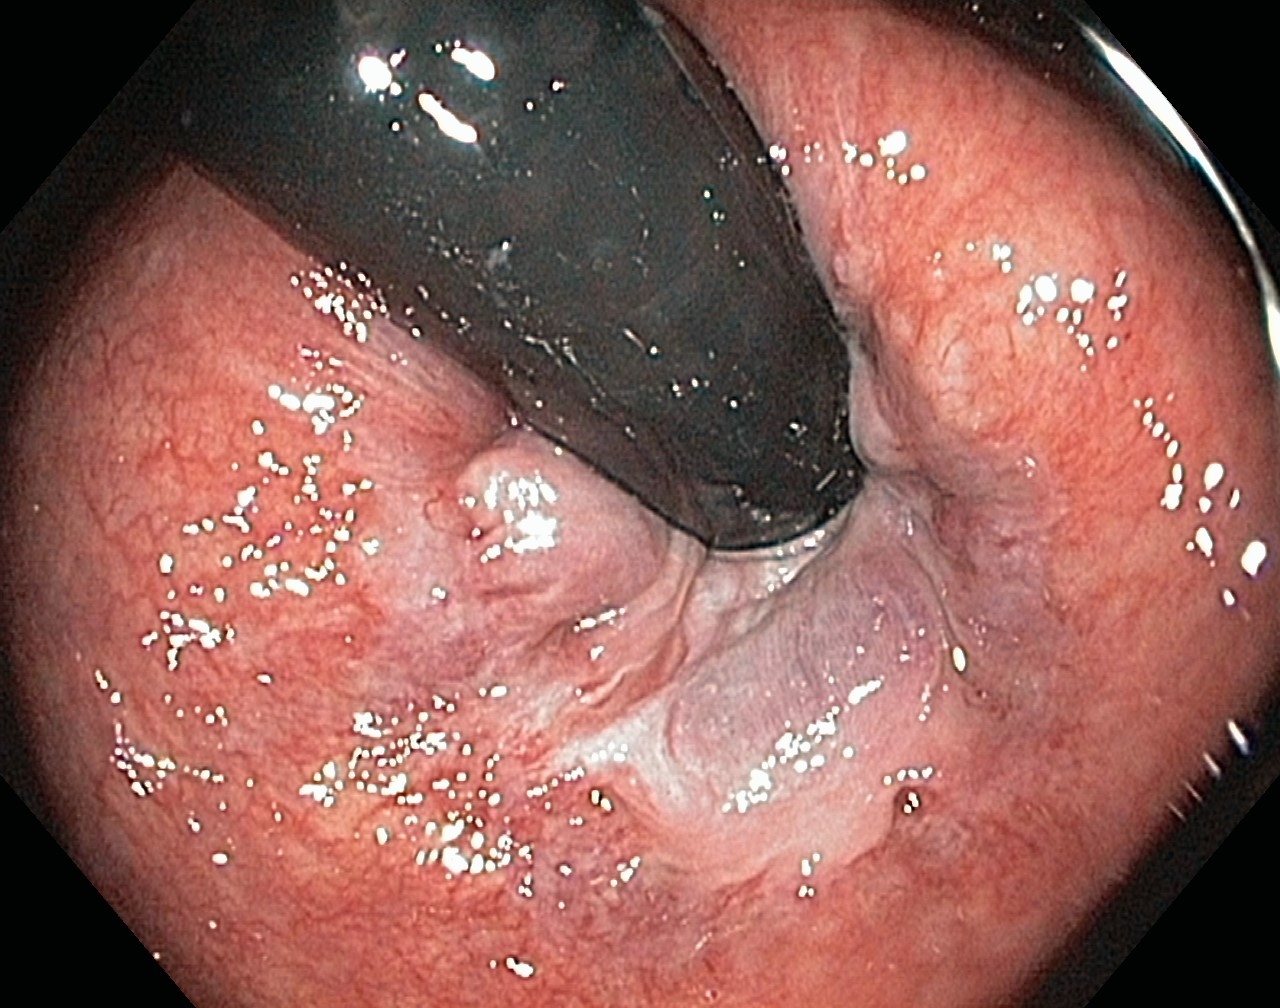

Linea dentata/anorectalis seen with the endoscope in an inverted position